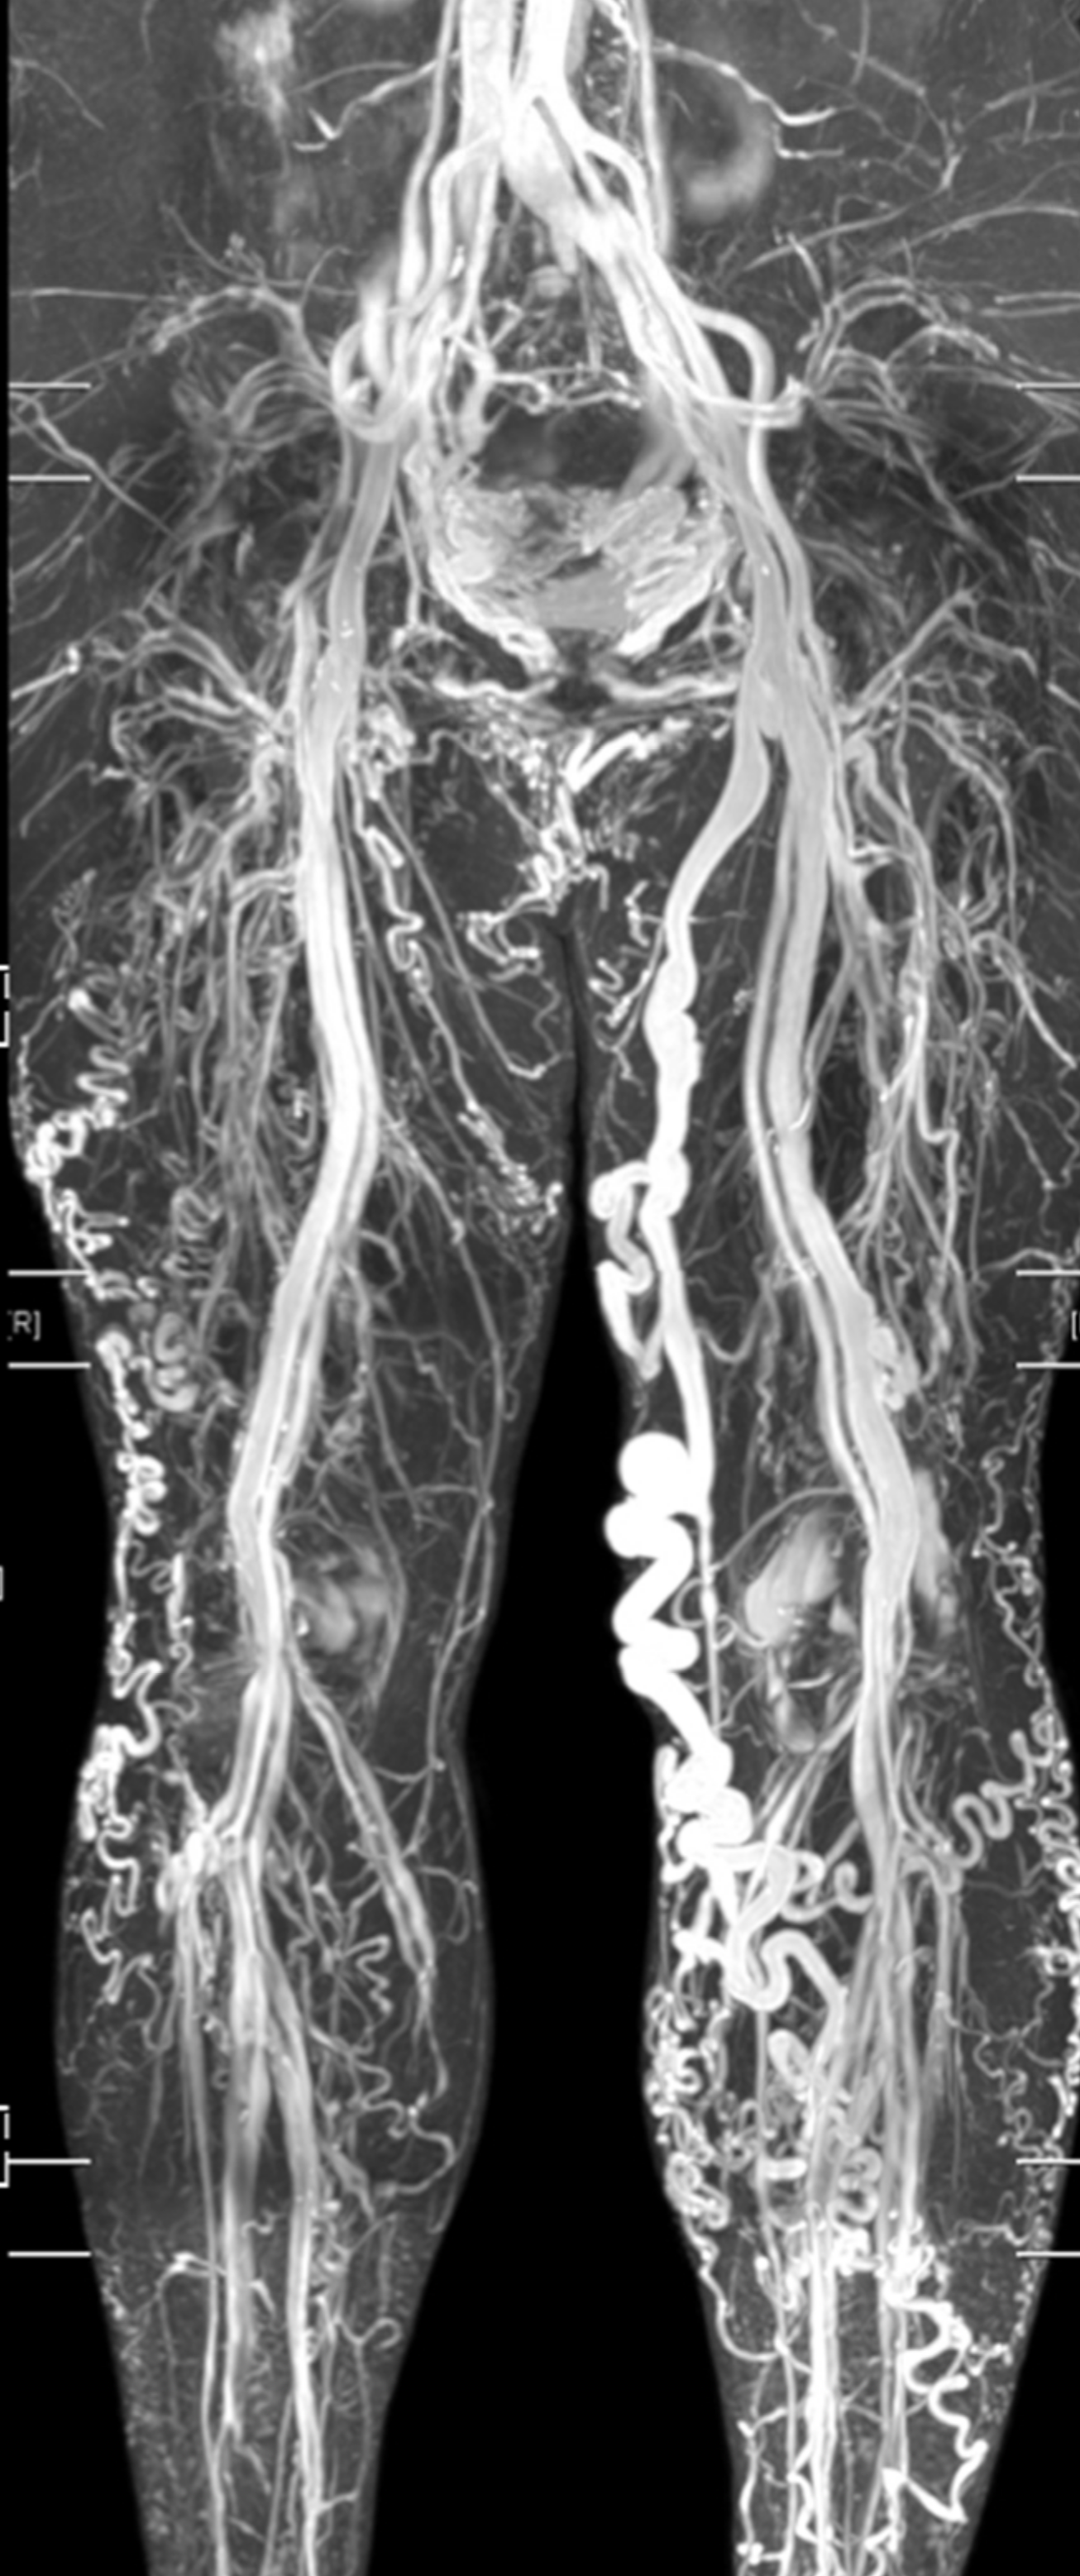

Ingeniører gør det muligt for lægen at rejse ikke-invasivt rundt i den menneskelige krop ved hjælp af medicinsk billeddannelse. Jan H. Ardenkjær-Larsen, DTU Health Tech fortæller om de nyeste teknologiske landvindinger inden for scanningsmetoder.